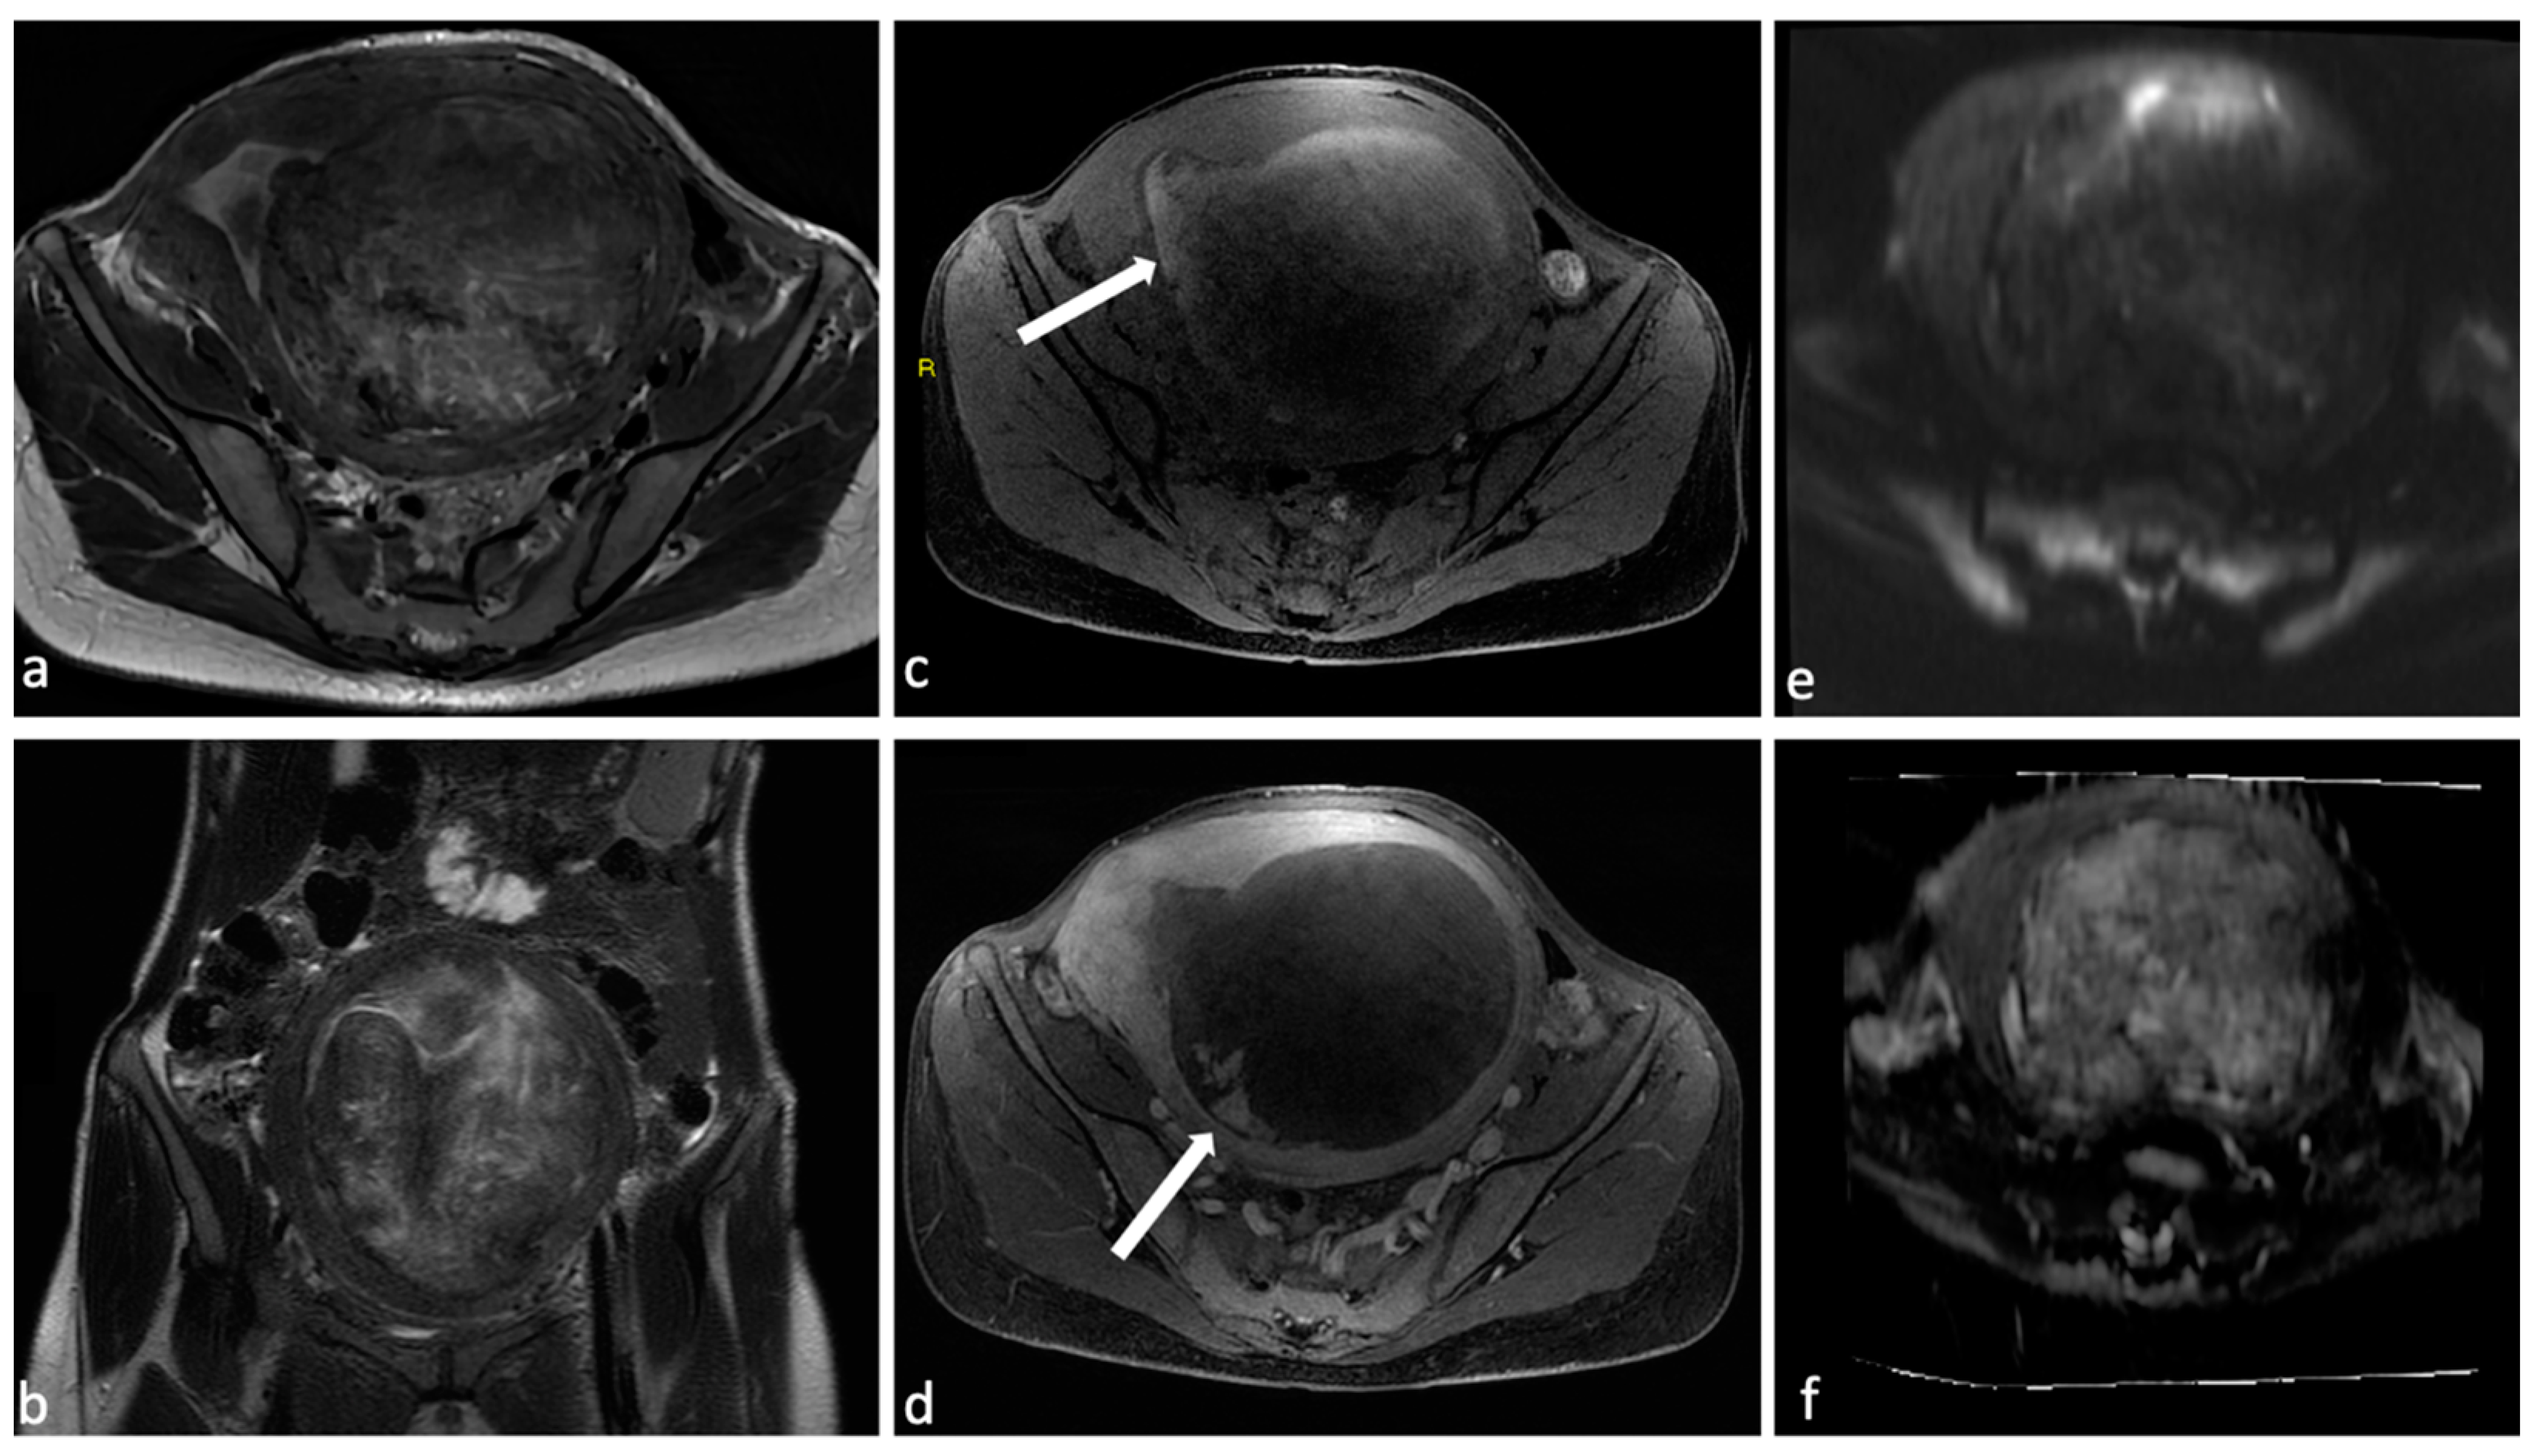

Figure 1.

Voluminous endometrial polyp. A 76-year-old woman with post-menopausal bleeding. MRI shows on T2 sequences (a,b) a voluminous mass within the endometrial cavity of intermediate signal intensity with cystic components and a fibrous core (arrow). The mass demonstrates absence of endometrial invasion on pre- and post-contrast T1 sequences (c,d) and low signal on DWI with high signal on the ADC map (e,f). These findings are suggestive of partially expelled endometrial polyp.